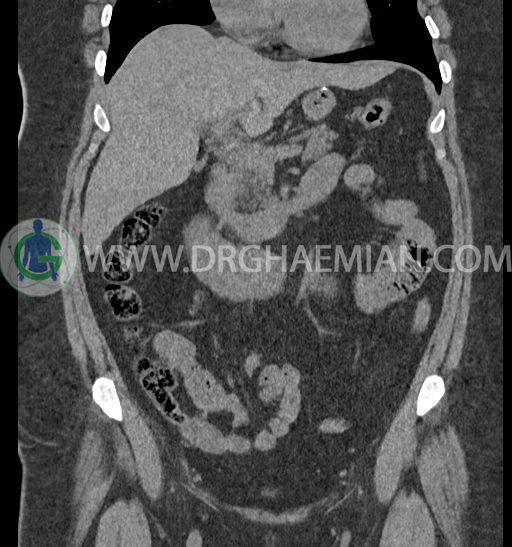

سی تی اسکن شکم و لگن با استفاده از اشعات ایکس تصاویر عرضی از ناحیه شکم و لگن ایجاد میکند. در این کیس کلیه نعل اسبی و سنگ کلیه مشاهده می شود.

در سی تی اسکن اسپیرال شکم و لگن بدون کنتراست (مولتی دیدکتور 16 با مقاطع ظریف و بازسازی های ساژیتال و کرونال) :

-horseshoe kidney

-حداقل سه سنگ 5mm در کلیه راست و یک سنگ 3mm در کلیه چپ بدون شواهدی از هیدرونفروز

-شواهد جراحی اسلیو قبلی در Body و فوندوس معده

-آپاندیس نرمال بصورت رتروسکال

مشهود است.